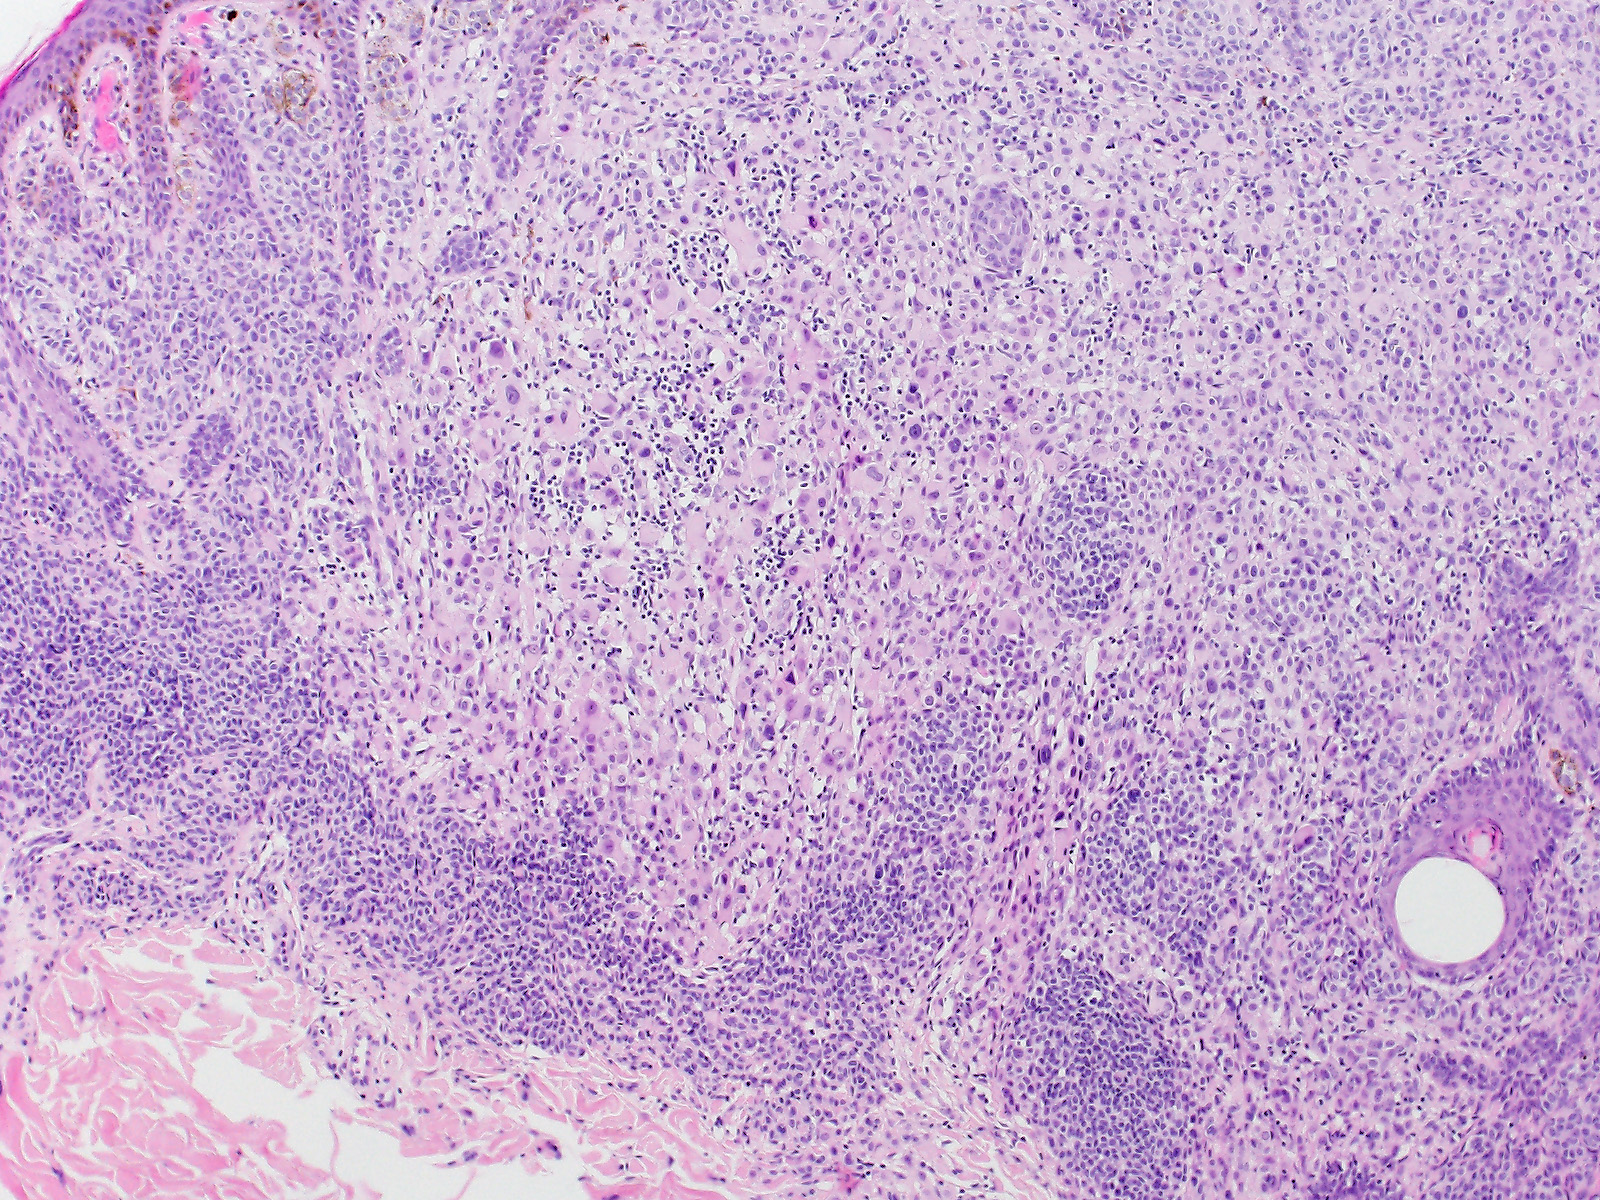

Biphänotypischer, überwiegend intradermaler Naevus mit einer kleinzelligen gewöhnlichen Naevuskomponente in den Randzonen und einer atypischen epitheloidzelligen Komponente. Die atypische Epitheloidzellkomponente besteht aus grossen Melanozyten mit reichlich glasigem Zytoplasma, klar definierten Zellgrenzen und grossen, vesikulären, leicht pleomorphen Zellkernen mit prominenten eosinophilen Nukleolen. Einige Zellen sind mehrkernig. An einigen Stellen sind reichlich tumorinfiltrierente Lymphozyten erkennbar.

Die grossen epitheloiden Zellproliferate zeigen einen Verlust der BAP1 Expression im Zellkern. Die Zellkerne des gewöhnlichen Naevusanteils sind positiv. Beide Komponenten sind immunhistochemisch positiv für die BRAF V600E Mutation.

In Wiesner's nevu, classic features of Spitz nevus, such as Kamino bodies, spindle-shaped melanocytes, epidermal hyperplasia and clefting around junctional melanocytic nests, are absent.

These tumors may be sporadic or appear multiple in patients with an autosomal dominant syndrome caused by germline mutations in BAP1. Both sporadic and Wiesner nevi in the familial syndrome show BRAF V600E mutation and loss of nuclear staining for BAP1.

Wiesner's nevi may present as a pure large epithelioid cell proliferation or as in this case as a combined lesion in association with a conventional nevus.